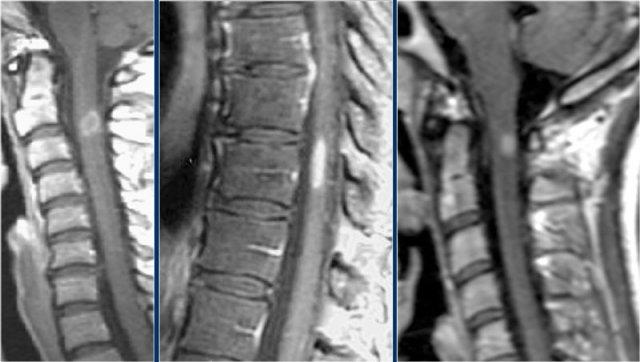

Bệnh Xơ Cứng Rải Rác

MS: tổn thương khu trú đoạn ngắn hình nêm ở cột sau tủy sống kèm theo các tổn thương chất trắng quanh não thất điển hình.

Trong tủy sống có một số tổn thương bờ rõ, nhưng cũng có một số tổn thương bờ không rõ, mờ nhạt.

Hình ảnh cắt ngang cho thấy vị trí ở phía lưng và hình dạng tam giác điển hình.

Trên các hình ảnh sau tiêm thuốc tương phản từ, không thấy ngấm thuốc.

Các tổn thương MS hoạt động ở tủy sống có thể ngấm thuốc, nhưng không phổ biến như các tổn thương hoạt động ở não.

Khi phát hiện tổn thương ở tủy sống, việc chụp thêm não cũng rất hữu ích.

MRI não cho thấy các tổn thương quanh não thất và một tổn thương ở thể chai.

Các vị trí này rất đặc trưng cho MS.

Ở một bệnh nhân khác có các tổn thương không đặc hiệu trong tủy sống.

Chỉ dựa vào khảo sát cột sống đơn thuần, chúng ta có một chẩn đoán phân biệt rộng.

Tuy nhiên khi khảo sát thêm não, sẽ rõ ràng rằng chúng ta đang đối mặt với MS.

Trên hình ảnh cắt ngang, các tổn thương MS thường có hình tròn hoặc hình tam giác và nằm ở phía sau hoặc phía bên.

MS là bệnh “bắt chước vĩ đại” và cũng có thể nằm ở phía trước như ở bệnh nhân này, người có tổn thương ở vị trí điển hình (mũi tên xanh) nhưng cũng có tổn thương ở phía bụng của tủy (mũi tên đỏ).

Điều này không phổ biến, nhưng bạn không thể loại trừ MS.